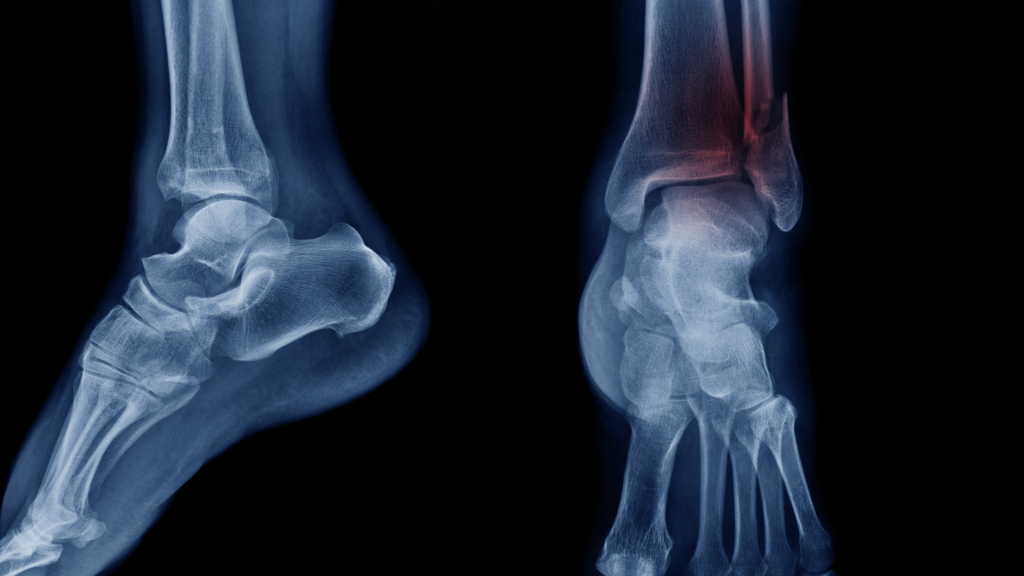

An X-ray of two legs, one with a broken ankle.